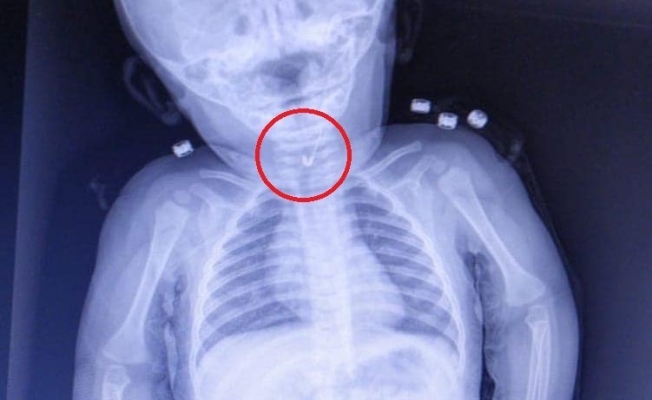

Tekirdağ’da 7 aylık bebeğin yemek borusundan ucu açık çengelli iğne çıktı.

Tekirdağ’da 7 aylık bir bebek, yemek borusuna çengelli iğine kaçması sonucu Tekirdağ Devlet Hastanesine sevk edildi. 7 aylık erkek bebeğin yutup yemek borusuna takılan açık çengelli iğne Tekirdağ Devlet Hastanesi’nde yapılan girişim ile başarıyla alındı. Gastroenterolojik Cerrahi Uzmanı Dr. İhsan Gündüz ile Anestezi Uzmanı Dr. İbrahim Çetin’in yaptığı operasyon sonucu bebek sağlığına kavuştu.